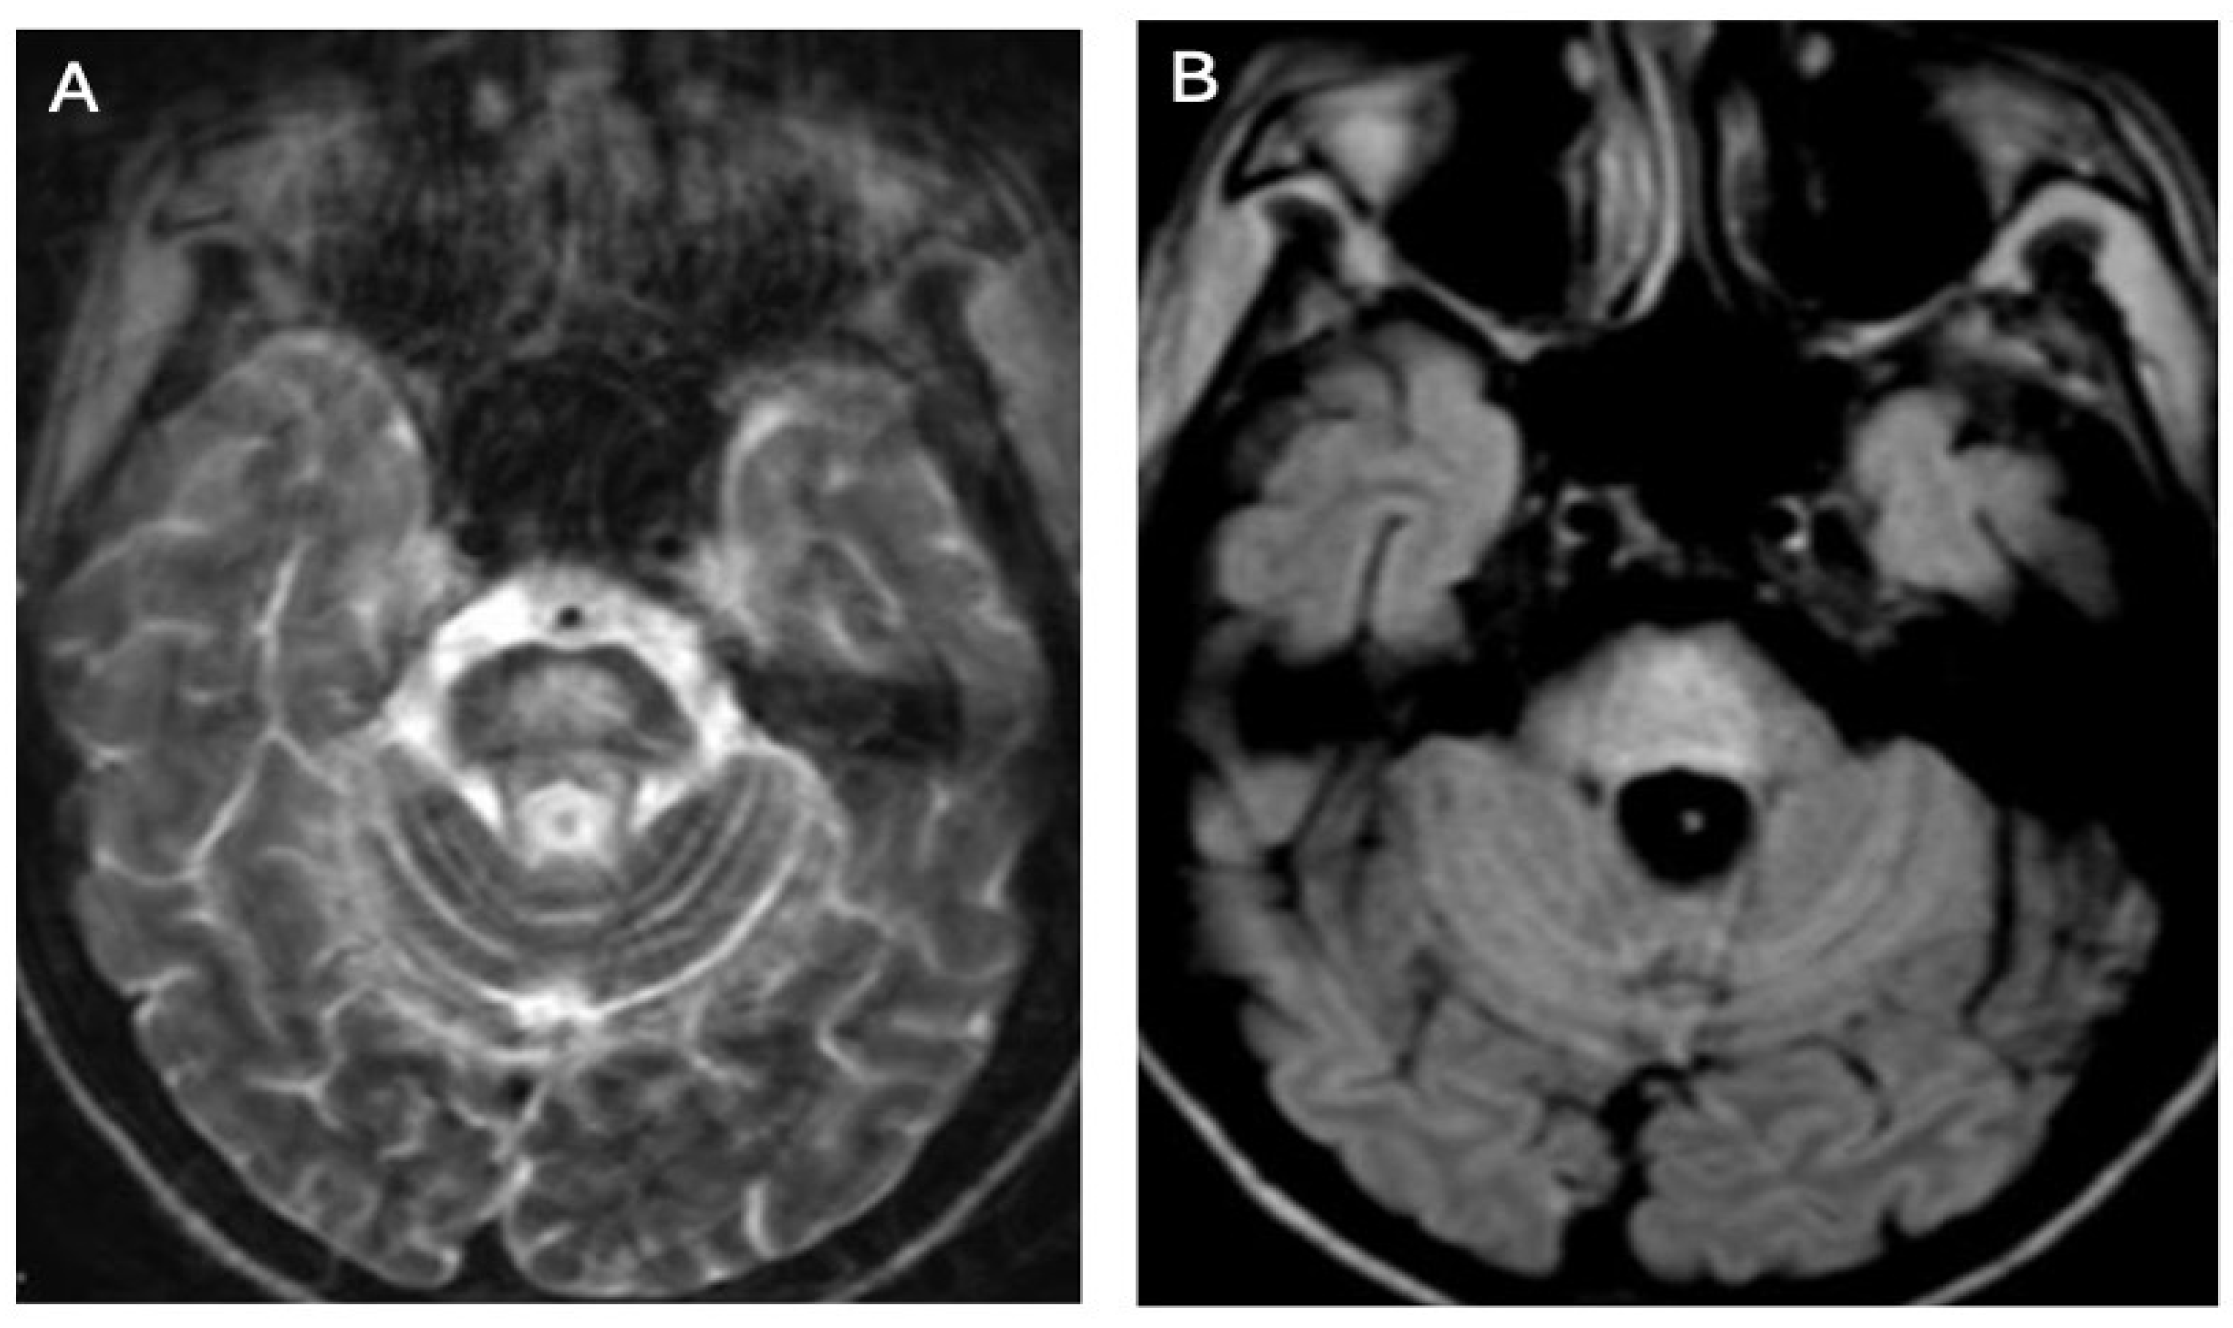

3.1. Classical Brain MRI Examination in WD Patients